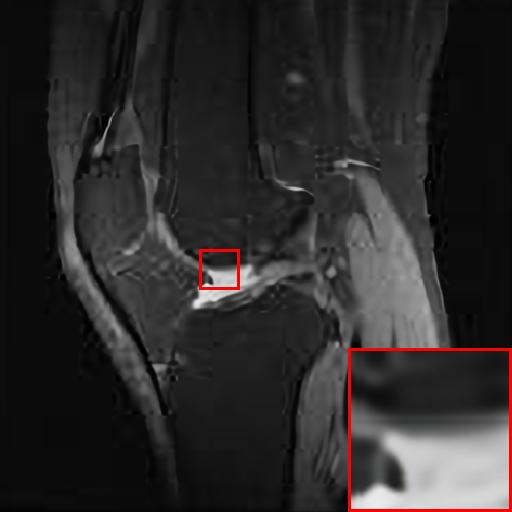

Figure 4: Reconstruction results of each algorithm for abdominal MRI images.

We likewise give the visualization comparison results for each comparison algorithm, as shown in Fig. 3 and Fig. 4. It can be seen that the reconstructed images based on bicubic interpolation and deep learning based EDSR and WDSR both show oversmoothing phenomenon and some loss of detail information of the images. In contrast, our T-GAN performs better for the reconstruction of detail information due to the texture Transformer structure.